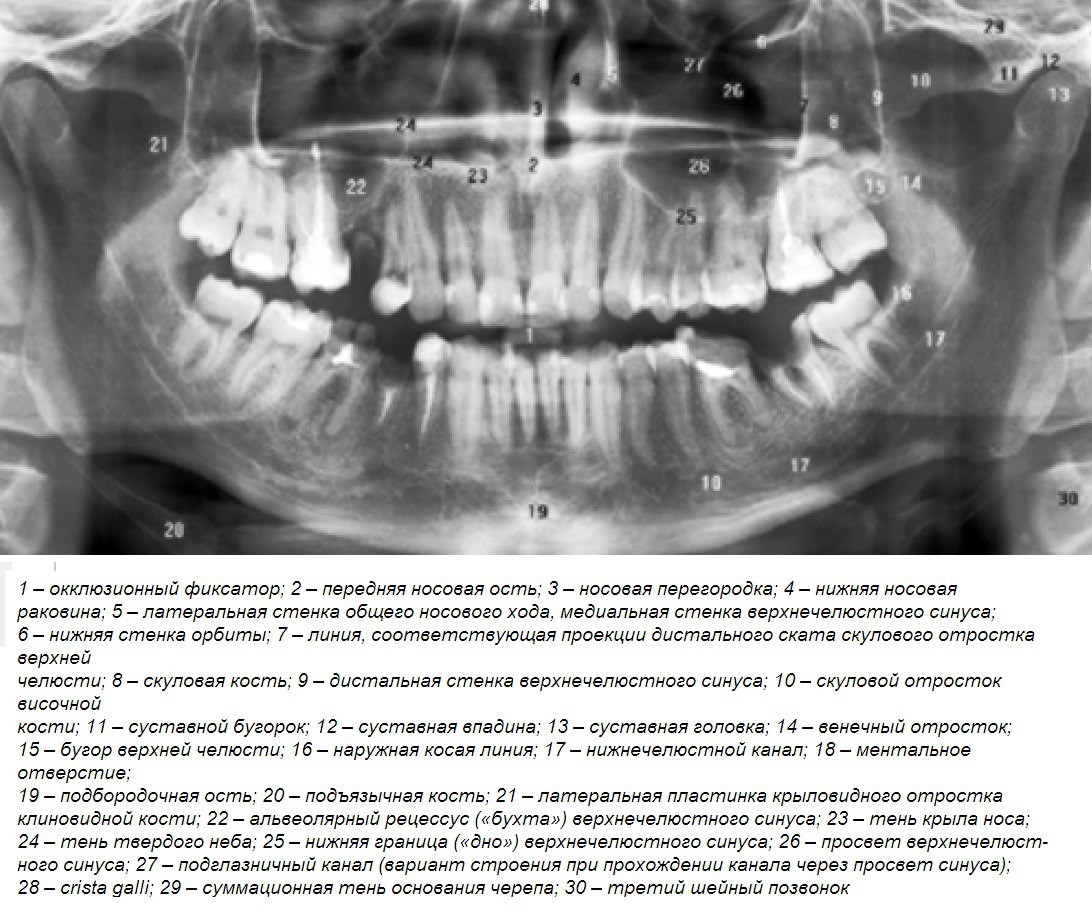

Дентальные снимки и диагностика кариеса